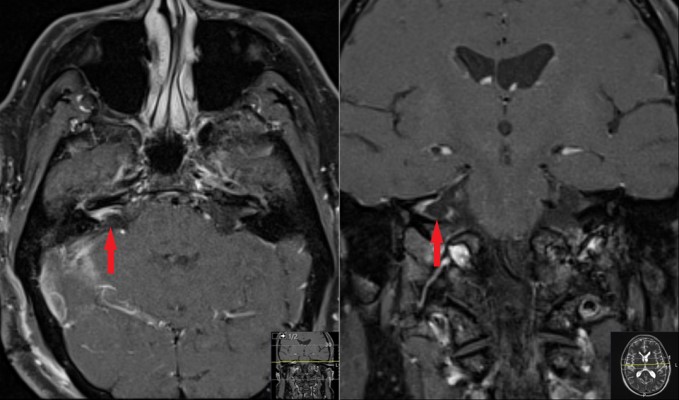

Contrast enhanced MRI of the brain 3 years prior to presentation. It shows a definitive tumor in the right IAC (red arrows) on axial (left) and coronal (right) views. It has shown definitive growth compared with prior study (Figure 1)